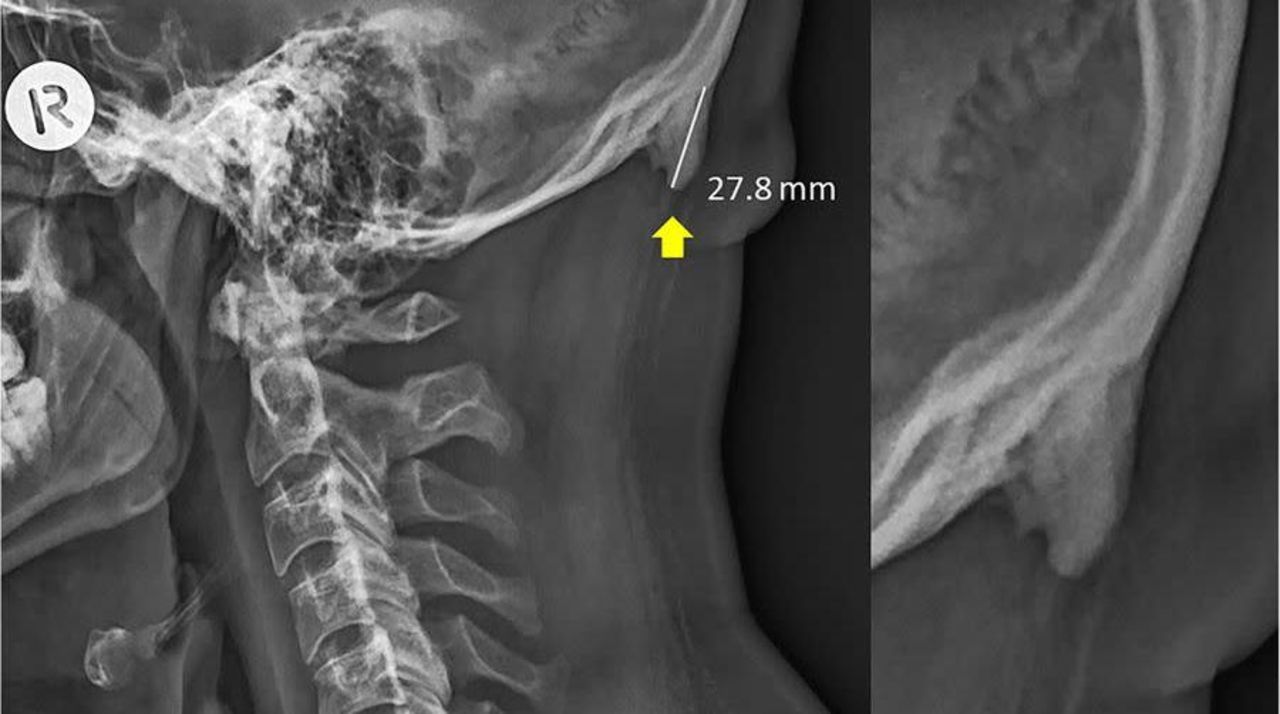

Mobilanvändning leder antagligen inte till att du får horn Även om ny studie föreslår detta Mobilanvändning leder antagligen inte till att du får horn Foto: Sahar and Sayers / Scientific Reports Forskare på australiensiska University of The Sunshine Coast har i några rapporter påvisat att vissa människor har ett hornliknande ben i sitt bakhuvud som man uppger är förstorat hos en del av befolkningen. I en av sina rapporterar spekuleras det om att denna förstoring kan ha skett på grund av personernas användning av mobiltelefoner.Rapporten har blivit flitigt citerad den senaste veckan där vissa medier skriver att man kan få "horn" av att använda mobilen. Detta verkar vara något överdrivet och i rapporten finns inga faktiska bevis för att så är fallet rapporterar flera källor. Att det hornliknande benet skulle ha blivit större är en hypotes man arbetar utifrån, inget som har kunnat bevisas överhuvudtaget skriver bland andra Gizmodo som skriver: